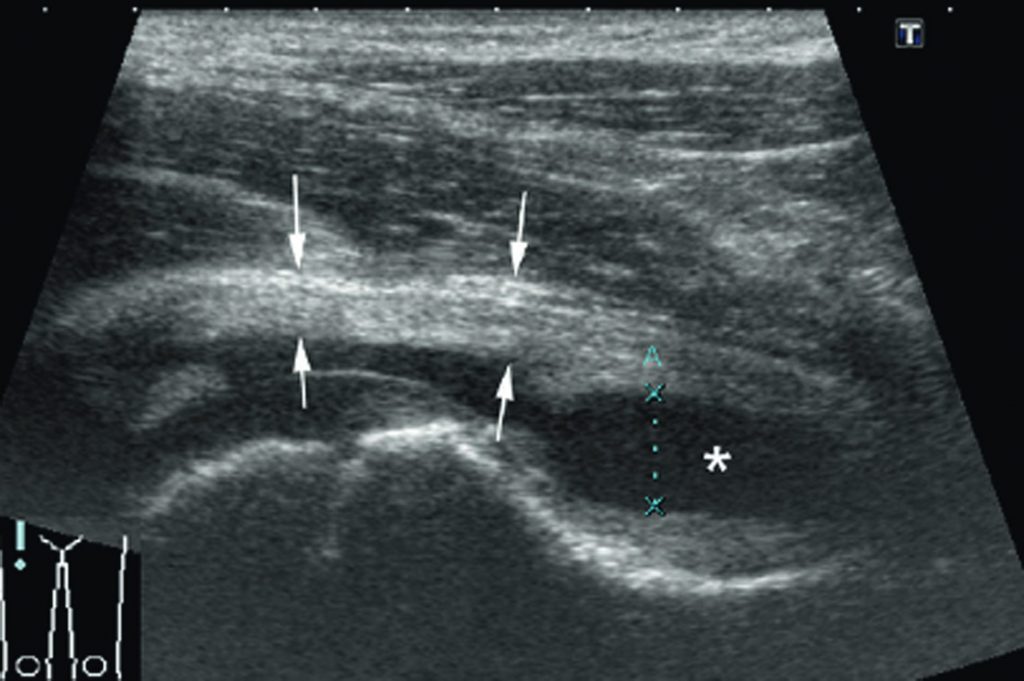

Fig. 78.2 Arthrite septique de la hanche droite.

Échographie montrant un épanchement articulaire (étoile) et un épaississement de la synoviale (flèches).

Source : CERF, CNEBMN, 2022.

Elle permet le diagnostic (figure 78.2) :

- d’épanchement articulaire : liquide anéchogène intra-articulaire ;

- de synovite : synoviale épaissie, signal en doppler.